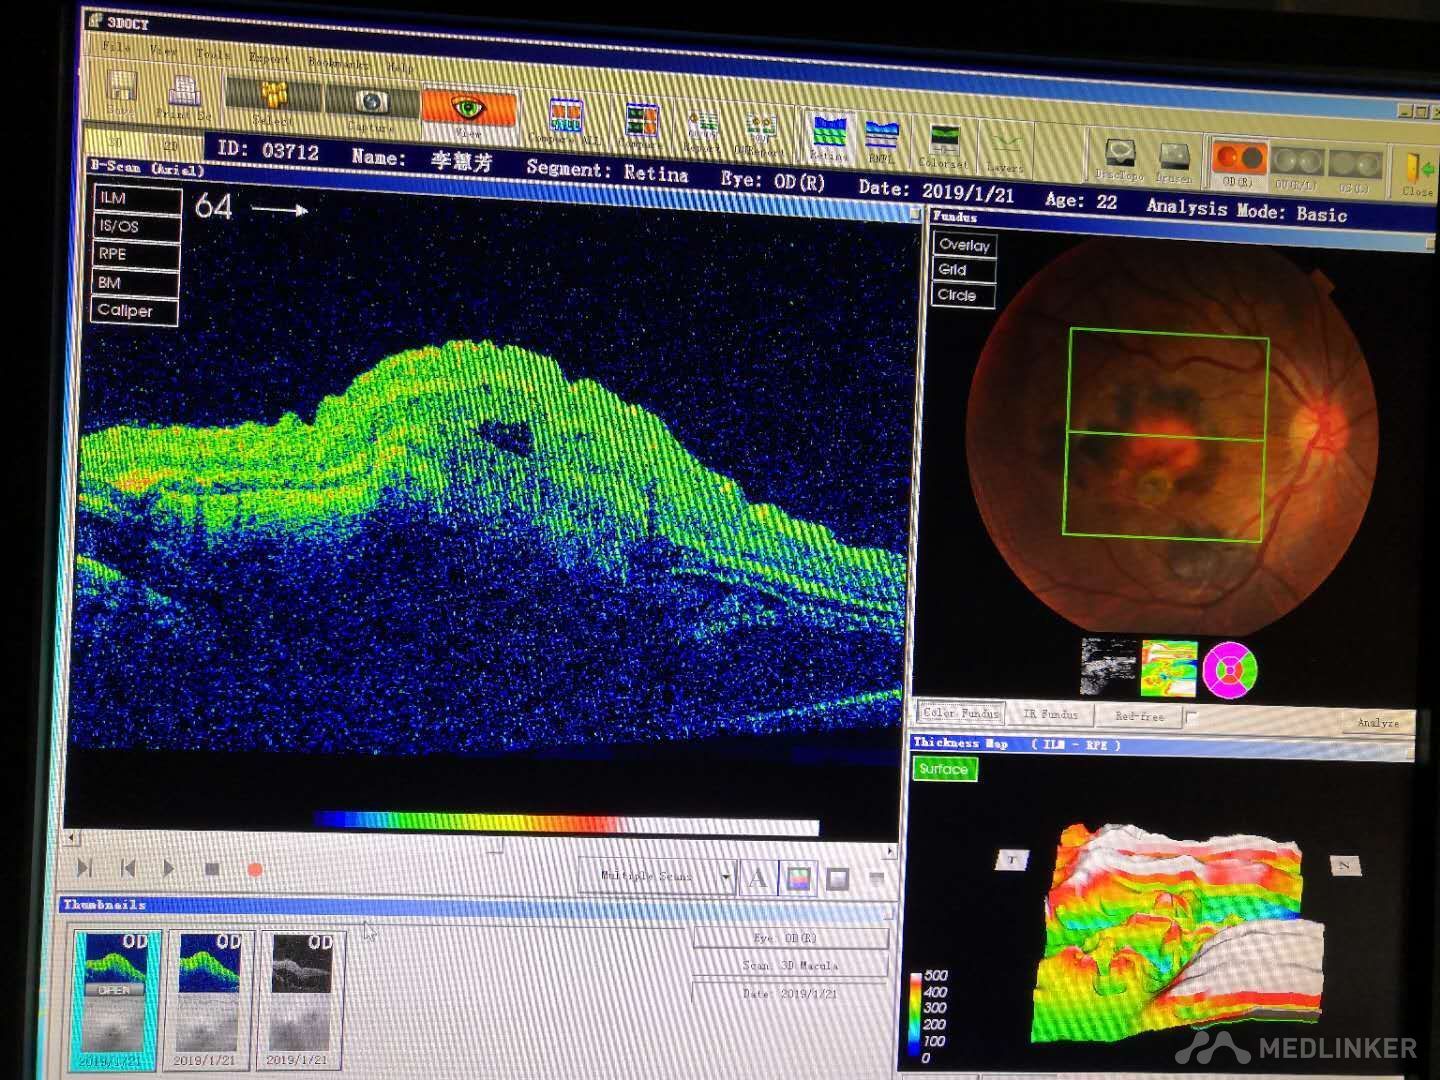

眼底出血(がんていしゅっけつ)は網膜表面の血管の破綻や閉塞することで起こる網膜の出血である。 出血の量自体は微小で貧血などの原因となるものではないが、重度の視力障害を来すこともある。

出血量、出血部位、出血位置、出血後の血行動態等により視力予後が変わる。

等に分類される。出血部位の色調・辺縁の性状にて分類可能である。

- 黄斑部出血

- 黄斑下出血

原因として代表的なものが糖尿病網膜症、高血圧性眼底、網膜中心静脈閉塞症、加齢黄斑変性などである。